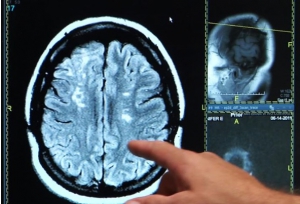

Les chercheurs de l'Université de Göteborg (Suède) et de l'University College London ont suivi durant 5 années, 700 femmes âgées de plus de 70 ans, exemptes de démence, dont 98 prenaient des suppléments de calcium. Au cours du suivi, ces participantes ont subi des tests d'imagerie afin de détecter les signes de maladie cérébrovasculaire, des lésions de la substance blanche ou les zones du cerveau ayant une mauvaise circulation sanguine- ce qui est associé à la démence vasculaire. Au cours du suivi,

La supplémentation en calcium déclencheur d'AVC chez les femmes déjà à risque élevé : Enfin, une analyse plus poussée montre que la prise de calcium n'a pas augmenté le risque de démence chez les femmes qui avaient pas eu d'AVC ou qui ne présentaient aucun signe de lésions de la substance blanche sur leurs scans du cerveau. L'analyse révèle que l'augmentation du risque de démence est concentrée chez les femmes sous supplémentation, à antécédents d'accident vasculaire cérébral, ou présentant déjà des signes de dommages aux vaisseaux sanguins dans le cerveau. Les résultats de cette étude observationnelle, mené sur un petit échantillon de femmes sous supplémentation, doivent être confirmés. Les chercheurs concluent ainsi : « La supplémentation en calcium peut augmenter le risque de démence chez les femmes âgées ayant une maladie cérébrovasculaire ». Cependant ces résultats alertent, une nouvelle fois, sur l'importance de discuter de telles supplémentations, qui ne sont pas anodines, avec le médecin traitant.